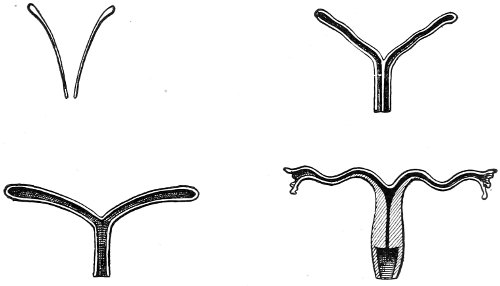

An accurate knowledge of the anatomy and mechanism of the female perineum is essential to an understanding of the nature and treatment of injuries to this structure. The anatomical structures lying between the anus behind and the symphysis pubis in front are those that most directly interest the gynecologist. Proceeding from 57 below upward, we find the following structures lying in superimposed planes: the skin, the superficial fascia, the deep layer of the superficial fascia, the transversus perinæi and the sphincter vaginæ muscles, the anterior layer of the triangular ligament, the posterior layer of the triangular ligament, the levator ani muscle (Fig. 19).

The injuries to the perineum that may result from childbirth are classified according to the position or the direction and extent of the laceration. They are as follows: slight median tear; median tear involving the sphincter ani; tear in one or both of the vaginal sulci; subcutaneous laceration of the muscles and fascia.

Slight Median laceration of the Perineum.—In this injury the tear takes place through the fourchette. Posteriorly it may extend as far as the sphincter ani muscle. Upward it may extend for an inch up the posterior vaginal wall. The appearance of this tear is shown in Fig. 33. It will be noted that, as this tear takes place in the median line, none of the muscles that support the perineum are involved, nor are the planes of fascia injured. The perineum is slightly split, and the insertions and origins of the muscles and the fascia are slightly separated. The supporting structures of the perineum and the pelvic floor are, however, uninjured.